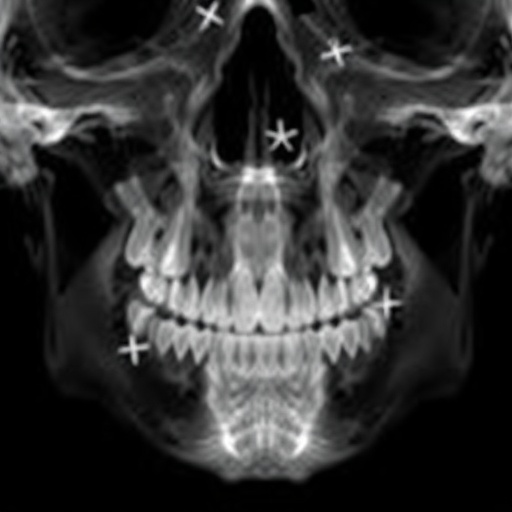

Orthodontic diagnosis traditionally relies heavily on the expertise of specialists interpreting lateral cephalograms—a type of X-ray imaging that provides a detailed side view of the craniofacial structure. Despite its crucial role, the process is often time-consuming and subject to human variability. Now, leveraging sophisticated machine learning methodologies, the new framework aims to standardize and expedite diagnostic procedures while maintaining, or even surpassing, human-level accuracy.

At the heart of the new technique lies a self-supervised pre-training model constructed from multi-center datasets of lateral cephalograms sourced from diverse clinical environments. This approach enables the model to learn robust and generalized structural features without requiring extensive manual annotations, which are often a limiting factor in medical imaging AI. By tapping into the vast amounts of unlabeled data, the system attains a deeper understanding of anatomical variations across populations.